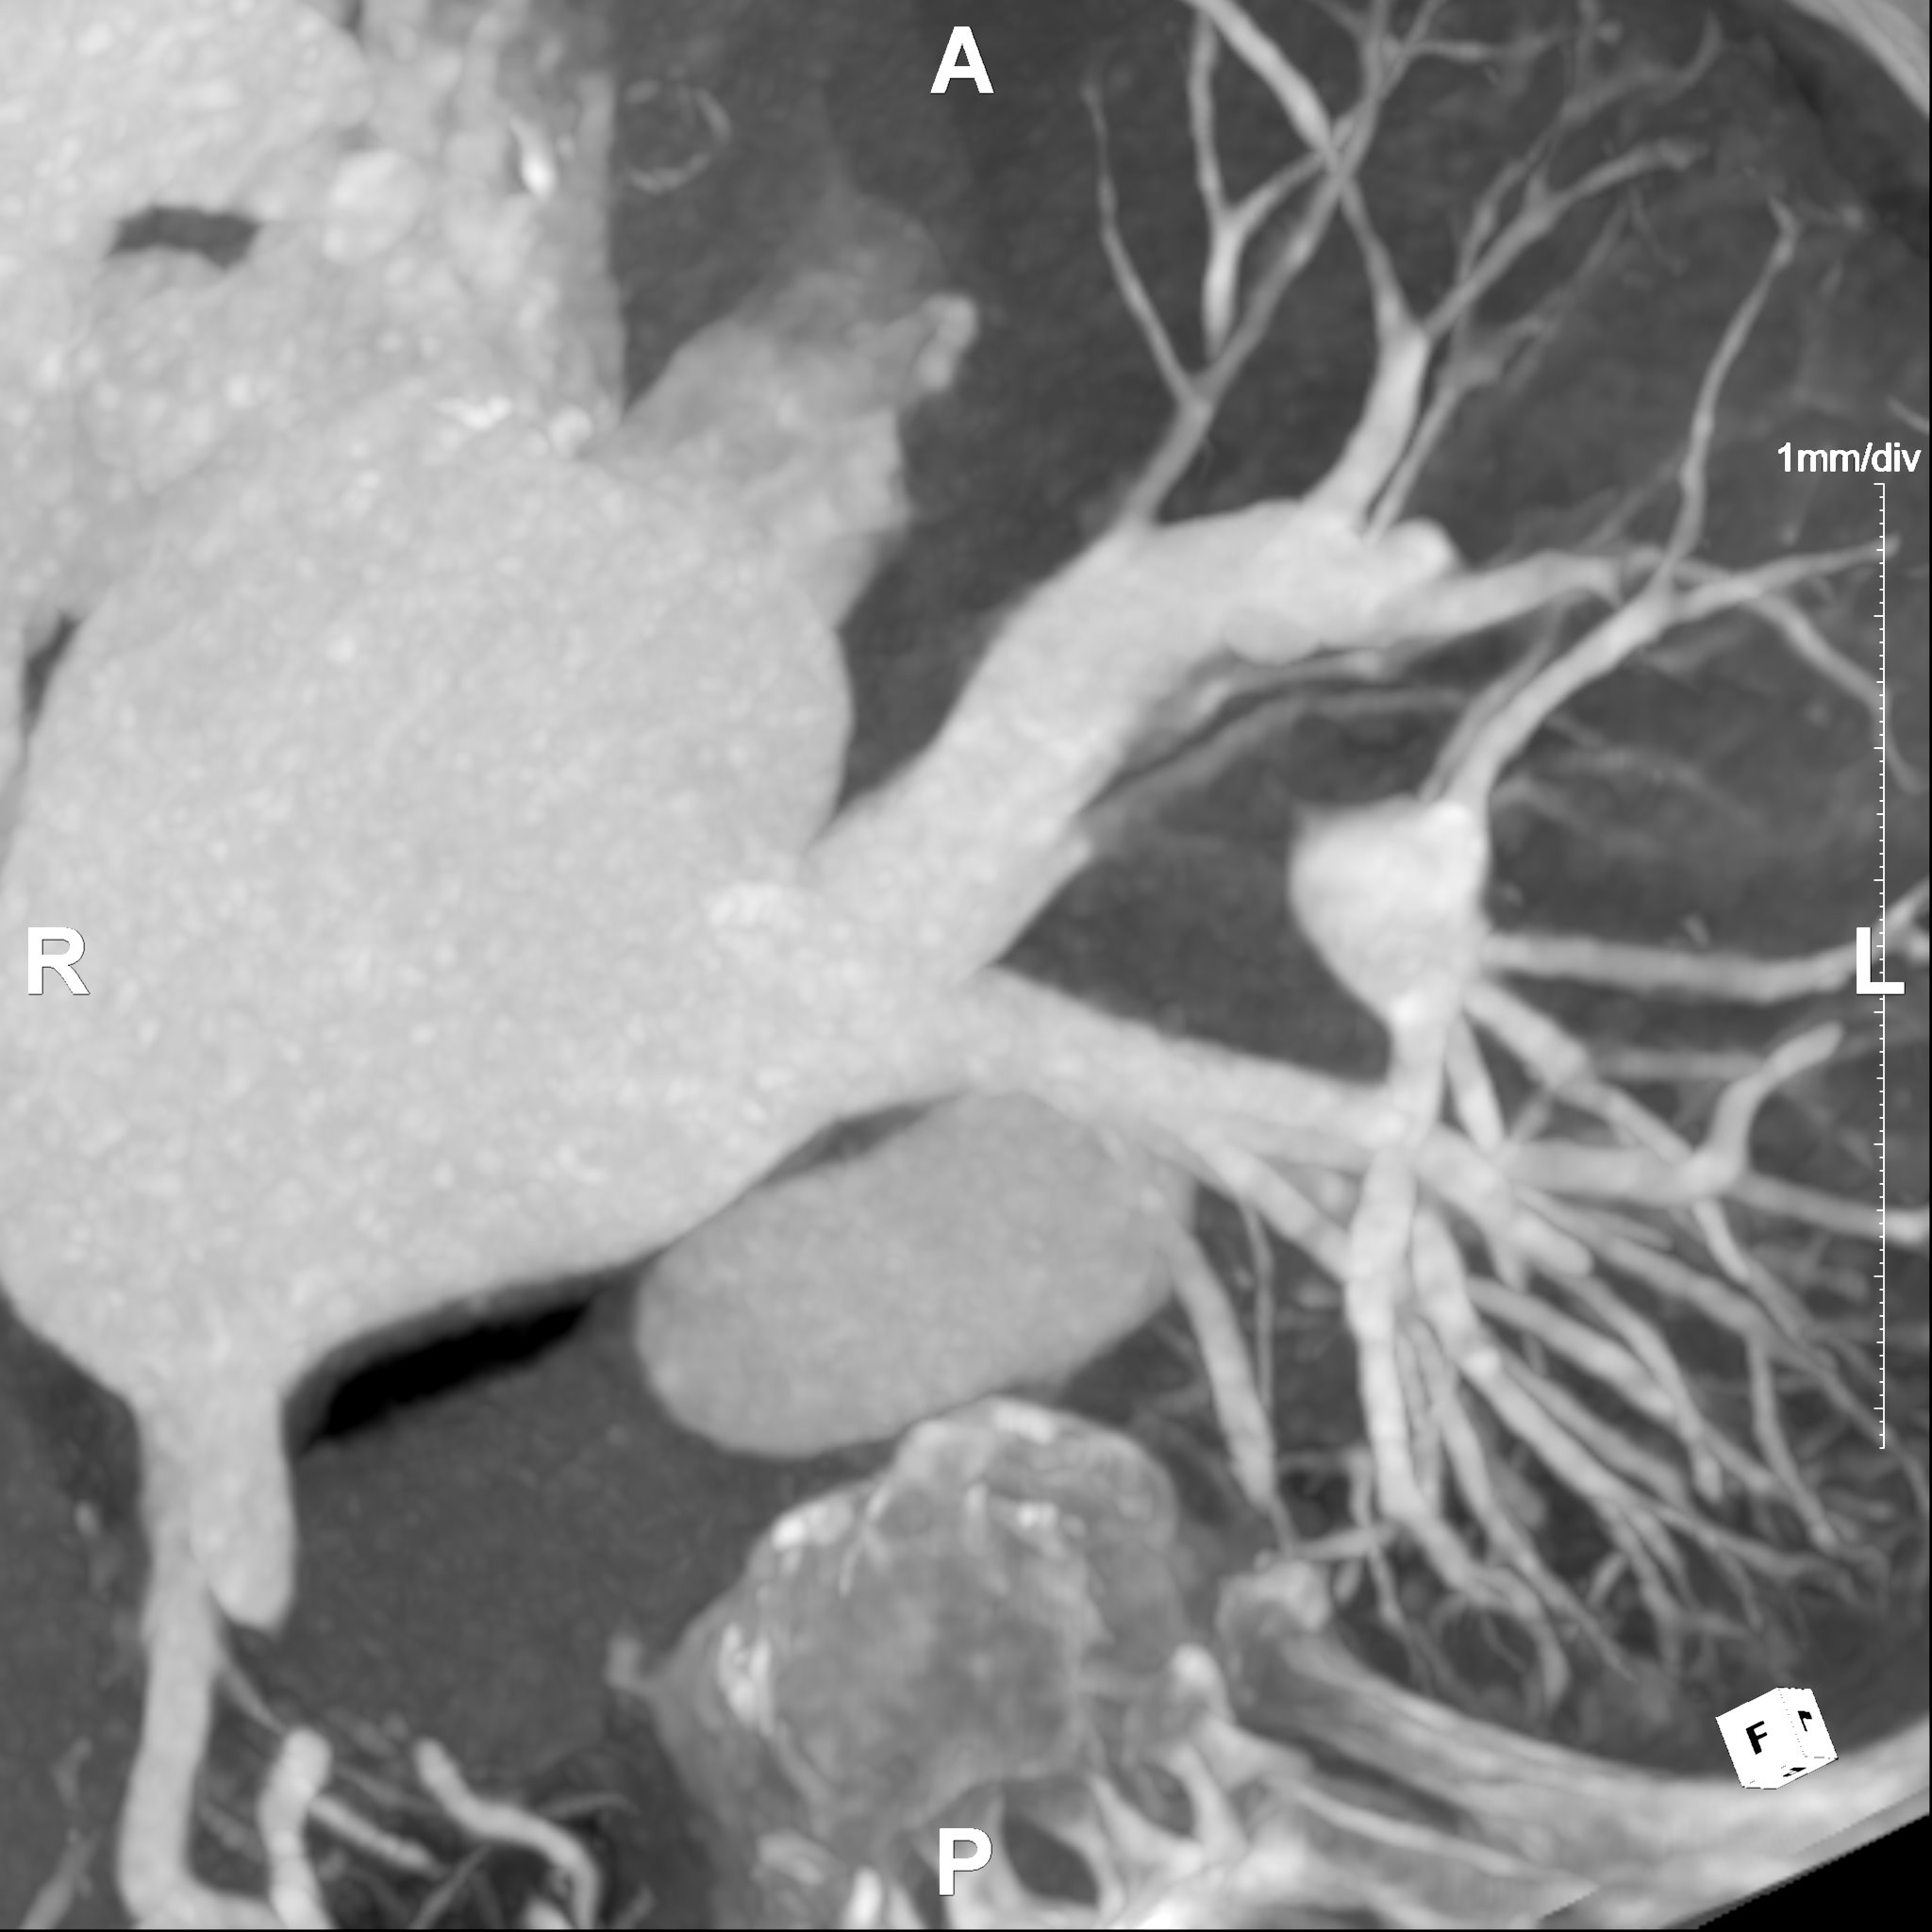

The Left Atrial Mapping service specializes in providing comprehensive left atrial imaging for the treatment of left atrial fibrillation (AFib) through ablation procedures. This service maps the pulmonary veins and their connections to the left atrium. This mapping can be used for pinpointing the origins of the erratic electrical signals that contribute to AFib. Maximum Intensity Projections (MIPs) enhance the visualization of the pulmonary veins by highlighting the brightest, most significant signals within the scan, corresponding to blood flow. This makes it easier to identify and target the specific areas responsible for AFib during the ablation process.

Additionally, the service provides measurements of orthogonal diameters and areas within the imaging data. These measurements offer an understanding of the pulmonary veins' dimensions and spatial relationships, providing insights for guiding the ablation procedure accurately. By analyzing these orthogonal measurements, specialists can assess the size and shape of the targeted areas, potentially ensuring a more focused and effective treatment. Post-ablation, the service continues its support by using these imaging techniques to assess for complications such as pulmonary vein stenosis.